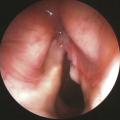

Les cancers des voies aérodigestives supérieures (VADS) représentent un groupe hétérogène de tumeurs se développant au niveau des lèvres, de la cavité buccale, du pharynx, du larynx ou des cavités nasosinusiennes. Il s’agit dans plus de 90 % des cas d’un carcinome épidermoïde, mais d’autres types histologiques existent : lymphomes,…

Les voies aérodigestives supérieures (VADS) constituent la partie haute des systèmes respiratoire et digestif. Elles sont constituées de muqueuses, soutenues par des éléments musculaires complexes et des structures osseuses et cartilagineuses dont l’analyse fine est nécessaire afin de déterminer l’extension des lésions qui s’y…

La chirurgie des cancers des voies aérodigestives (VADS) date de plusieurs siècles. Depuis les lambeaux brachiaux de Tagliacozzi au XVIe siècle (fig. 1), elle n’a cessé d’évoluer durant les deux cents dernières années avec la progression des connaissances anatomiques, physiologiques et les avancées technologiques.